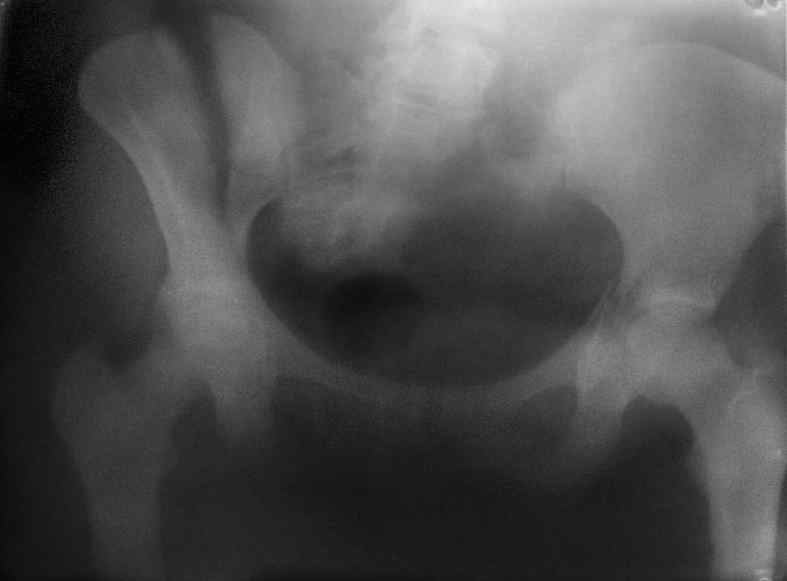

Здравствуйте, коллеги. Какие будут мнения по поводу лечения представляемой больной?

Молодая девушка 19 лет, травма 1 год назад, тогда же прооперирована.

В приложении снимки при поступлении и послеоперационные год назад.

Могу сказать одно: миграция винтов и нестабильность синтеза левого подвздошно-крестцовогоо сочленения очевидна.